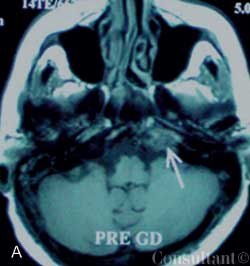

A 69-year-old man with an acute severe headache and nausea was brought to the emergency department. The patient was neurologically intact; an intracerebral hemorrhage was suspected.